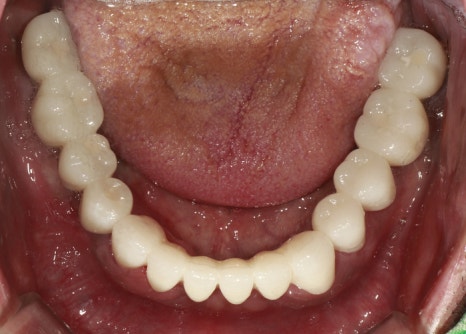

최종보철체결

촬영:2023년11월13일

마지막 보철 체결은 환자분께서 수면마취 없이

진행할 수 있을 것 같아 수면 없이 진행하셨습니다.

진료한 치아는 치아 모양과 배열 그리고 색상도

불규칙해 입 주변이 어두워 보였는데

임플란트와 크라운 보철로 치아 모양이 정돈되니

이제 제 나이보다 훨씬 동안으로 보이세요.

최종보철을 제작할 때,

환자분과 심도 있는 이야기를 하기도 하지만

환자의 생김새, 피부 톤이나 연령대를 고려해

치아 모양과 색상을 추천해 드리는 경우가 있어요.

평균적인 보철의 사용 수명은 약 10년~15년으로

여러 가지를 고려해 이번 환자분은 치아색상을 한 톤 밝게 제작해 드렸는데

이 부분이 환자분과 잘 어울려

진료 전 후 차이가 확연하게 달라진 케이스입니다.